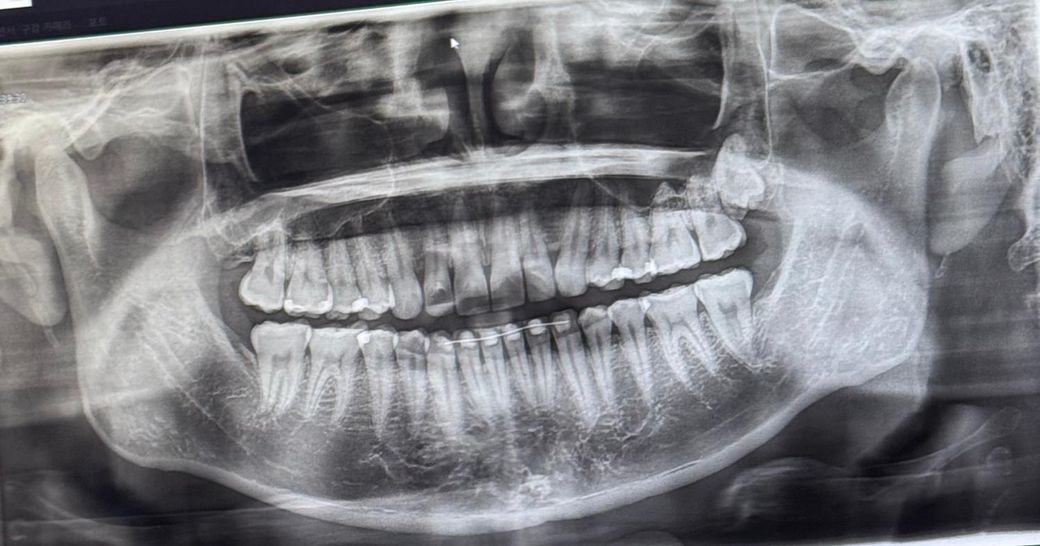

• 왼쪽 위 사랑니 발치가 필요한지 궁금합니다. 사진상으로는 오른쪽위에 있습니다. 치과병원마다 발치할 필요없다, 발치하는게 좋다고 의견이 달라 여쭤봅니다.

• 1번 째 사진

사랑니가 완전 매복상태라 특별한 이유가 없다면 발치를 하지 않으셔도 크게 문제가 되진 않을것같습니다.

지금으로서는 그냥 둬도 큰 문제는 없을 것으로 보입니다 뼈 깊숙이 자리잡은 사랑니는 안빼면 발생할 수 있는 문제가 낭 형성인데 지금은 그런 징후는 안보입니다